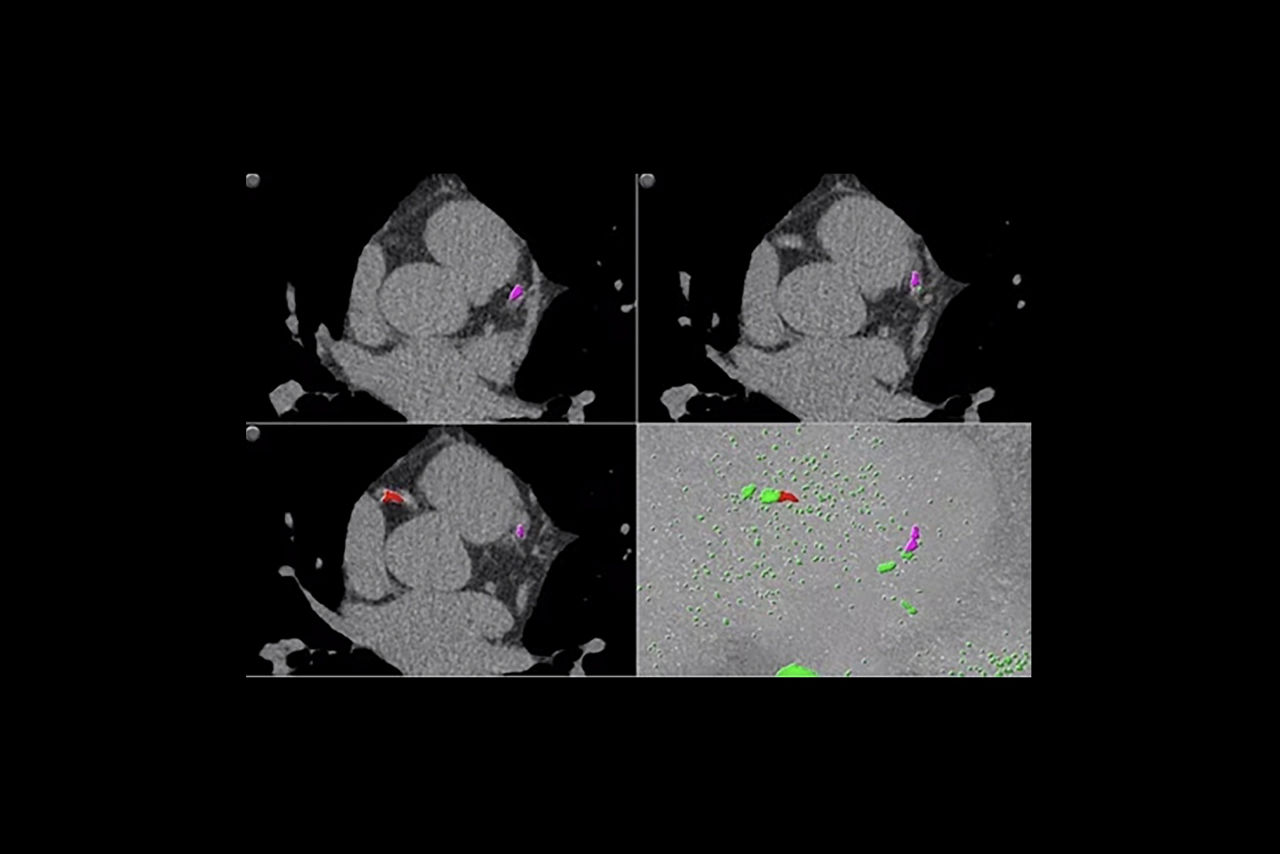

• AJ 130 scoring method uses conventional Agatston/Janowitz technique with a threshold of 130

• HU which is adjusted to the appropriate image slice thickness

• Volume scoring calculates volumes (mm3) of calcified plaque above the 130 HU threshold

• Mass scoring calculates mass (mg) of calcified plaque above the 130 HU threshold

• Individual and aggregate scores are computed for each artery type

• Provides two methods of calcium scoring